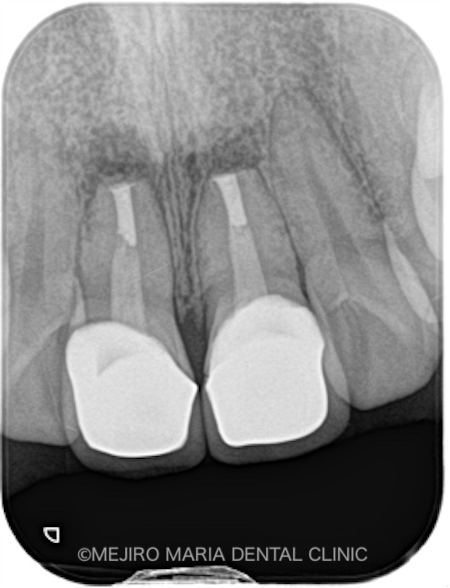

|術前レントゲン画像_治療後1-1.png)

|術直後レントゲン画像_治療後2-1.png)

|術後レントゲン画像_治療後3.png)

3ヶ月後には瘻孔(フィステル)と、術前に訴えていた違和感は消失し、術野の歯肉の治癒も良好であることを確認しました。レントゲンでも、根尖部付近の骨の再生が認められたため、予後良好と判断しています。